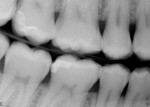

A 36-year-old man who works in the police force presented with a fractured disto-lingual cusp of tooth No. 2 and a stress crack on distal marginal ridge (Figure 1) that occurred due to a blow to his face while restraining a person who was resisting arrest. He complained of feeling sharp edges and experiencing sensitivity to cold while drinking and even while breathing. The patient requested a temporary fix because he was tight on time.

After examination, the author recommended a porcelain onlay and advised the patient that the treatment could be completed within the hour, which he readily accepted. The tooth was numbed, prepared, and imaged, and the onlay was milled, tried in, polished, and bonded all in approximately 45 minutes (Figure 2). The patient was very happy with the efficient, predictable, and esthetically pleasing outcome.